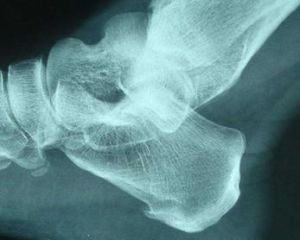

4.X線平片

早期階段,X線片大多正常,中晚期可見關節間隙不對稱性狹窄、關節面下骨硬化和變形、關節邊緣骨贅形成,關節面下囊性變和關節腔游離體等。X線片可分為五級。0級:無改變;1級:輕微骨贅;2級:明顯骨贅,關節間隙正常;3級:骨贅外關節間隙中度狹窄;4級:骨贅外關節間隙嚴重狹窄,伴軟骨下骨硬化。